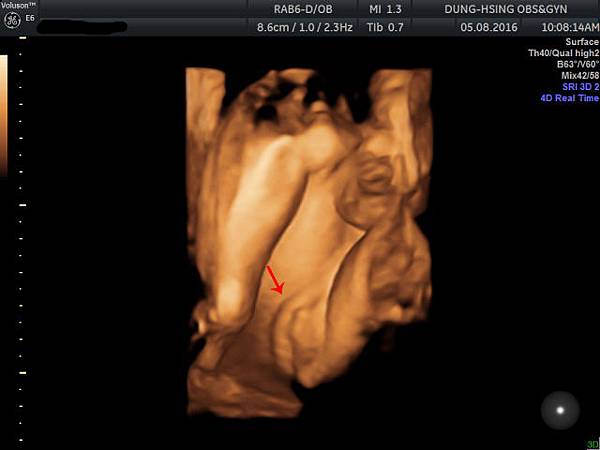

今天去照了4D超音波

主要是以嘗鮮為目的啦這機器跟高雄的產檢醫院滿類似的

順便看看寶寶到底長什麼樣子![]()

照片是她的腿骨測量右下角寫著重量1906g評估是32W.....還有點小隻表示我要繼續再吃養胎中藥

強而有力的心跳145下/分鐘不過技術人員說是148快接近男寶寶的心跳了

記得當初萱是140而已

(豬爸爸說:根本男生, 幹嘛出來是女生)

小妹妹的臉大鼻子厚唇跟萱萱剛出生時有點像

妹妹在笑

這是陰唇喔非常清楚的特徵

林豬爸爸:"我的小花生!!!"(吶喊樣)

哎唷趙醫生早就已經說是女生了還在自我催眠